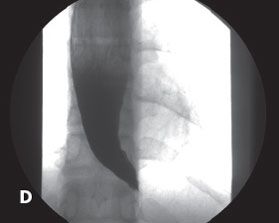

Esophagogastroduodenoscopy revealed a mildly dilated lower third of the esophagus (A). CT demonstrated a dilated esophagus (B). A barium swallow showed the classic “bird’s beak” appearance of the distal esophagus with proximal esophageal dilatation (C and D). A diagnosis of achalasia was made.